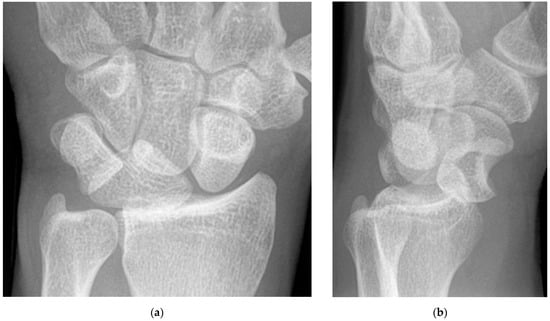

Lateral wrist radiographs provide a wealth of information in the assessment of carpal alignment but are susceptible to suboptimal projection at the time of imaging which frequently limits assessment. A well-positioned lateral wrist radiograph should demonstrate the volar surface of the pisiform midway between the ventral surface of the capitate and distal scaphoid. When this has been accomplished, intercarpal alignment is most accurately demonstrated. In this scenario, with the wrist in the neutral position (neither flexed nor extended) a line that bisects the center of the articular surface of the radius drawn along the long axis of the radius should align with the axis of the lunate and capitate. Deviation of the lunate or capitate away from this line is an indicator of carpal instability [2]. When this concern arises, the scapholunate and capitolunate angles should be measured. The scapholunate angle is determined by a line along the long axis of the scaphoid (roughly parallel to a line tangential to its ventral surface) and a line drawn along the mechanical axis of the lunate which bisects its proximal and distal surfaces (perpendicular to the tips of the distal cup). The normal limits of the scapholunate angle are between 30° and 60°. The capitolunate angle is determined by the same lunate axis line previously described compared to the long axis of the capitate. The normal limits of the capitolunate angle are between 0° and 30° [10]. Any measurement outside the normal range for these two angles is suggestive of carpal instability.